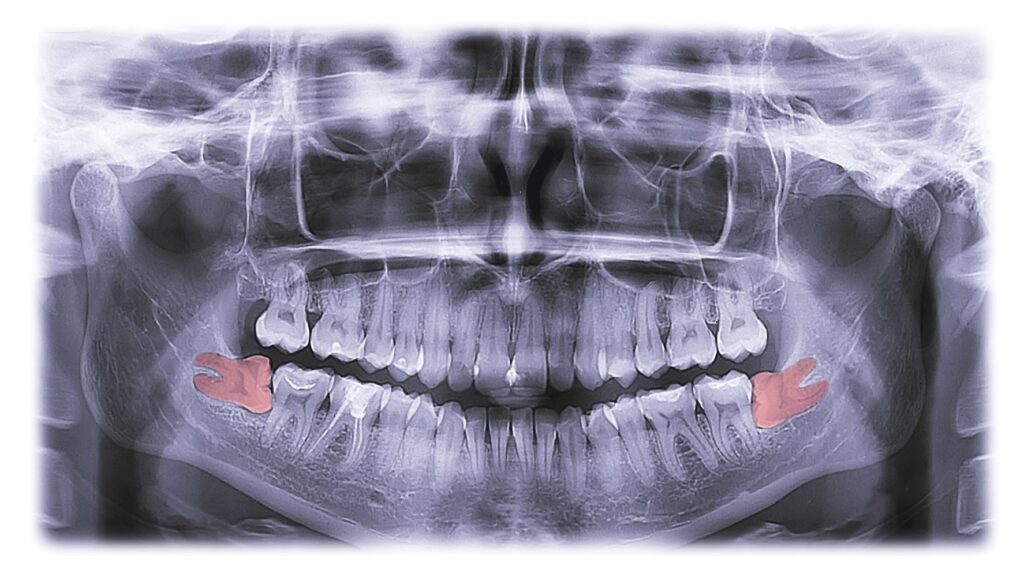

There are typically 4 of these large molars; one for each quadrant of the mouth. Today, they’re considered a vestigial feature because they don’t serve a functional purpose, and can cause dental problems when they show up. As a result, many providers recommend having them removed before they can become more troublesome. In fact, the extraction procedure is so common among teens that many consider it a rite of passage into adulthood.

Your oral surgeion can take X-rays to help determine how many wisdom teeth you have and whether they think removal will be required based on your unique circumstances.